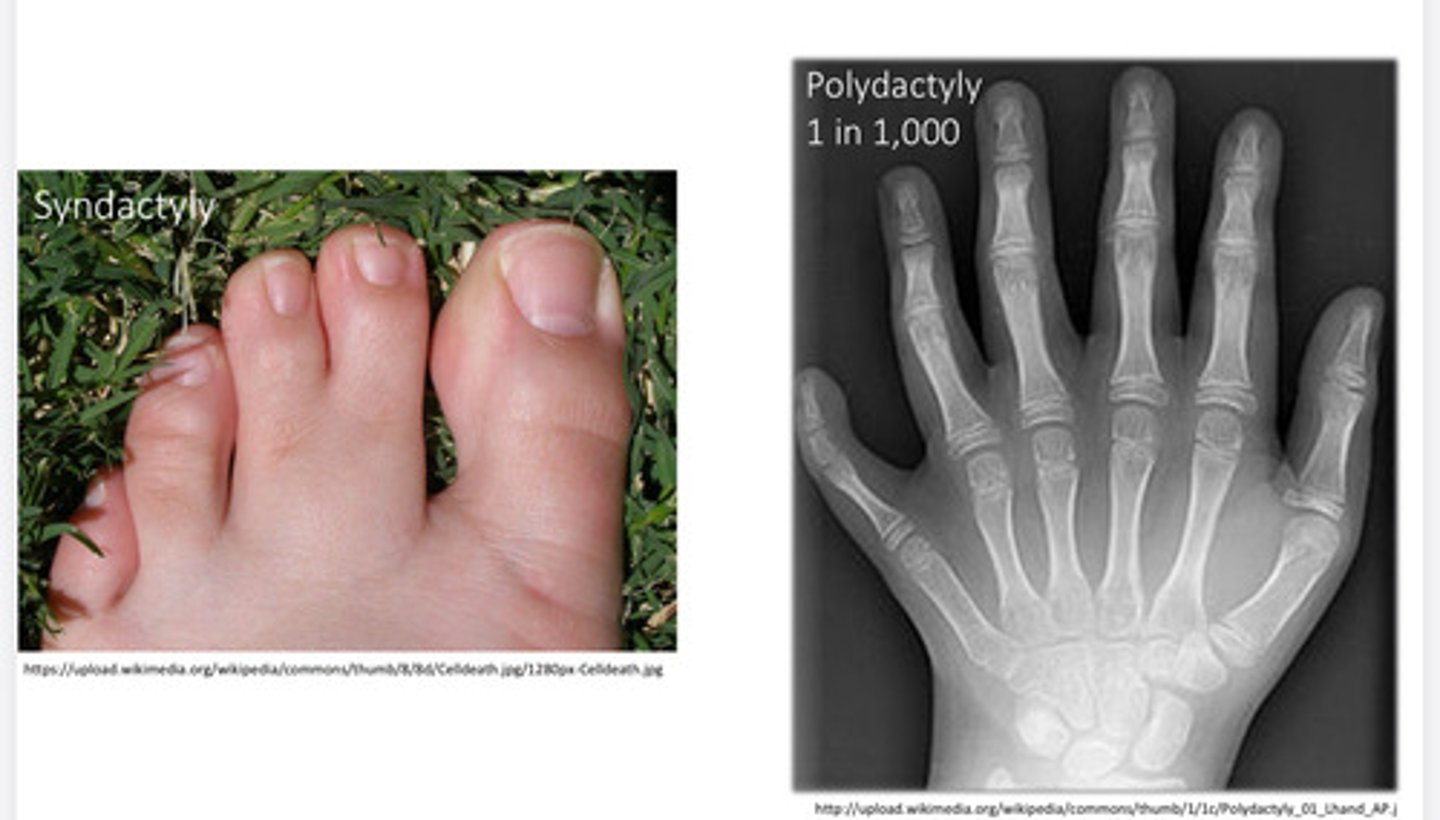

What is Dysostosis?

developmental anomaly of bone or cartilage

Dysostoses

Skeletal disorder that results from abnormal bone patterning, genetic or environmental. Extra digits or fusion of digits